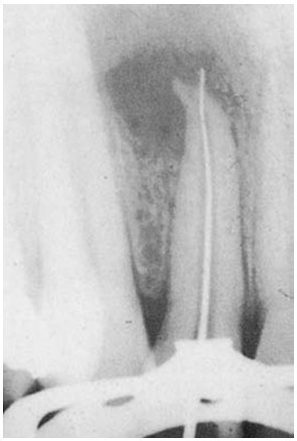

Jaką sytuację kliniczną przedstawiono na poniższym zdjęciu rtg?